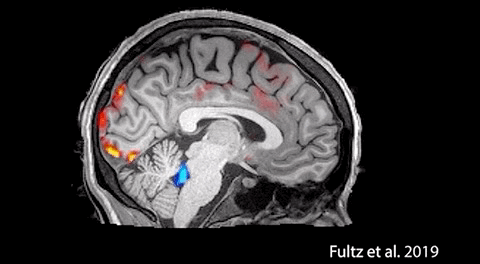

白天工作时,大脑会产生代谢废物,晚上睡眠时,大脑进入“清理模式”,洗掉白天积累的有害物质,让大脑恢复活力。2019年,波士顿大学的一项研究,清晰地描绘出睡觉时脑脊液清除代谢废物的完整过程。

波士顿大学研究发现脑脊液的工作过程,图源:《Coupled electrophysiological, hemodynamic, and cerebrospinal fluid oscillations in human sleep》